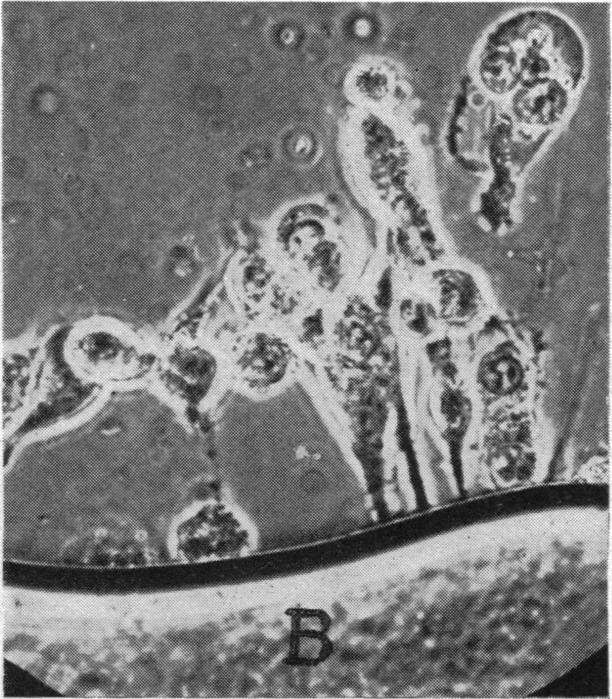

The dormant cancer cell.